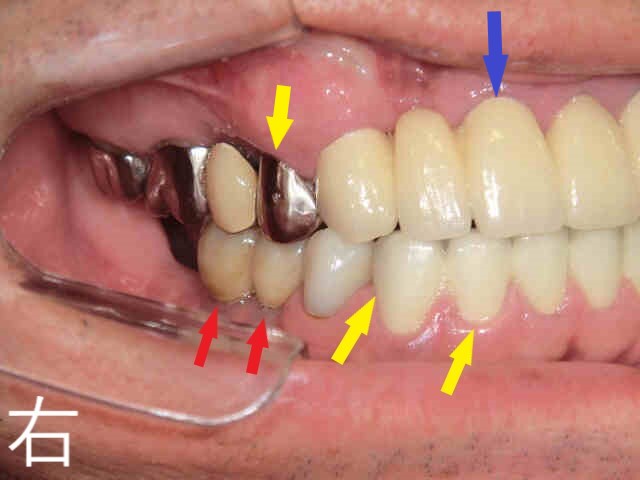

《下顎の状態》

同様に残根歯が複数確認され、保存が困難な部位が散見されました(黄色矢印部位)。

《奥歯の咬合状態》

左右の奥歯についても、上下で残根状態の歯が咬合しており、このままでは補綴物(被せ物や入れ歯)を入れることが困難な状況でした。